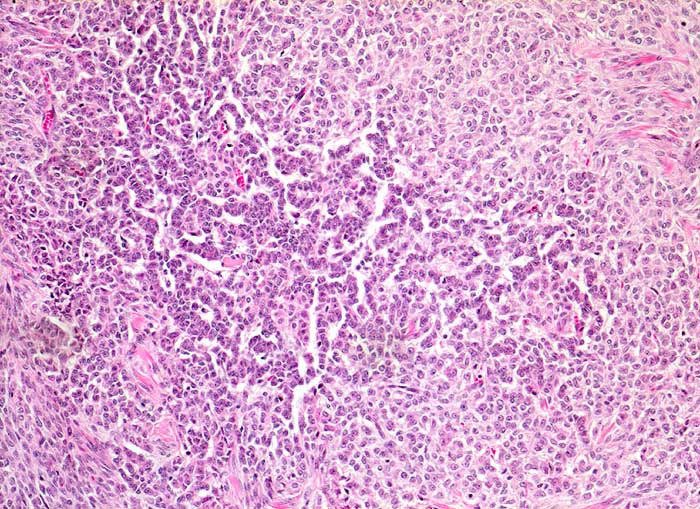

AP/ Granulosazelltumor des Ovars

Granulosazelltumor des Ovars

Ovar

Morphologie